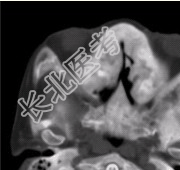

- [材料题] 患者女,25岁,左侧面部肿块,突眼10余年。CT表现如下图。

C、骨纤维异常增生症